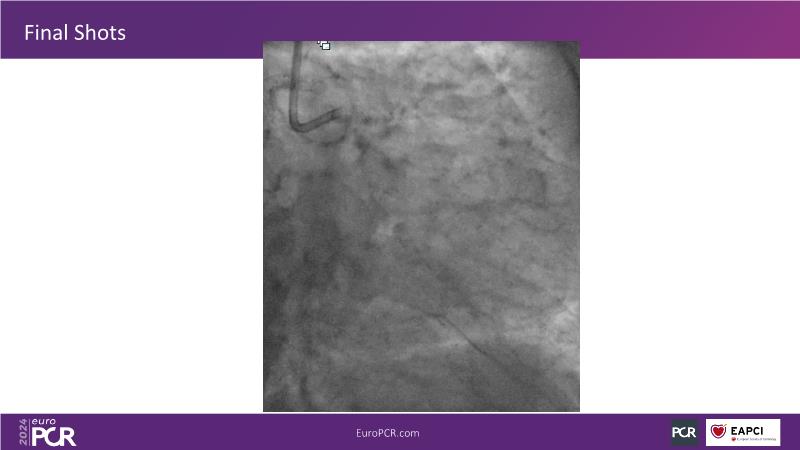

From innovation to reality: the impact of Cre8 EVO technology on complex PCI

This session is a good opportunity to delve into the contemporary technical and clinical complexities surrounding complex PCIs in challenging patient cases. Explore the necessary tools and treatment strategies to enhance peri-procedural and long-term clinical outcomes, and follow discussions on the unique technologies of Cre8 EVO in complex PCI scenarios.